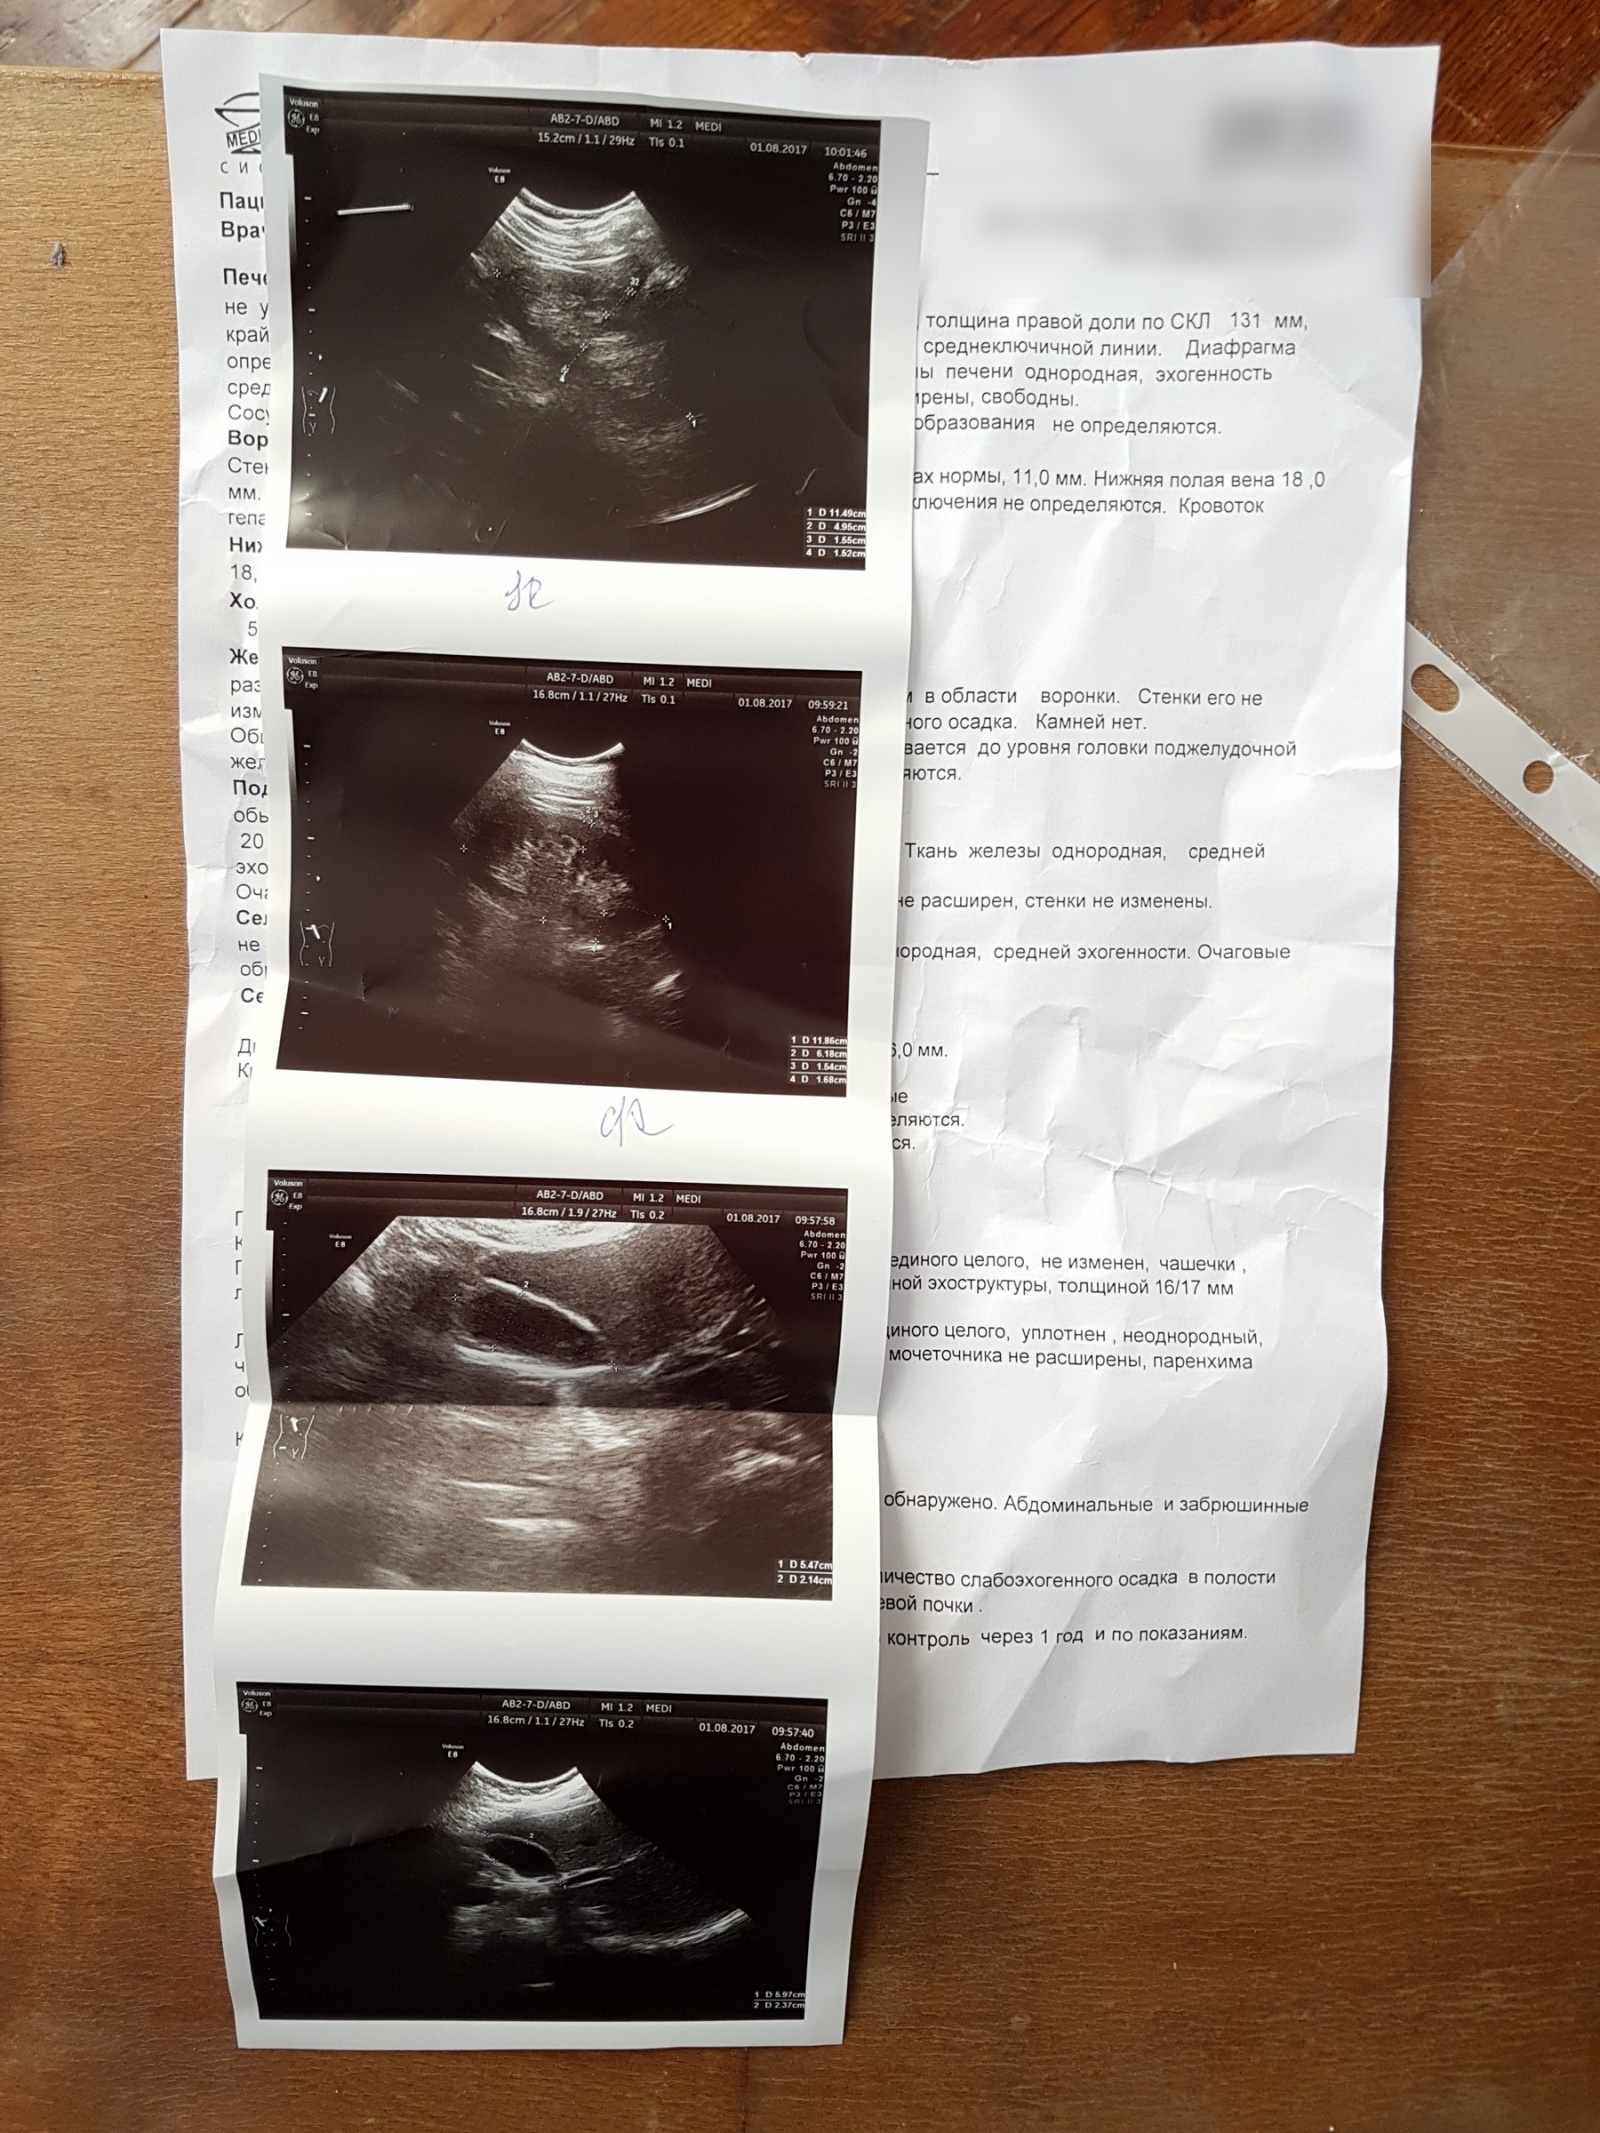

Я хожу к терапевту раз в 2 года. Последний раз был в этом году в августе, приведу для примера с фото как все происходило. Цель примера — показать, что это нужно и важно.

Мои анализы и рекомендации врача (аккуратно - много фото)

По результату назначила анализы крови в минимальном наборе + мочи + УЗИ.

Посмотрев их заранее и проанализировав на приеме рассказала, что все супер, жить буду, но:

1. запасы железа приближаются к нижней границе (я не ем мяса и поэтому она назначила этот анализ) и хорошо бы попить железа

2. кой чего (на картинке ниже) желательно попить для поддержки моего ливера (рассказывала точно, но так как я ей доверяю, то не запоминал)

3. один параметр Эозинофилы выше нормы и значит у меня или аллергия на что-то, или, так как я по полгода живу в Азии и Индии, паразиты.

Поэтому назначила дополнительные анализы.